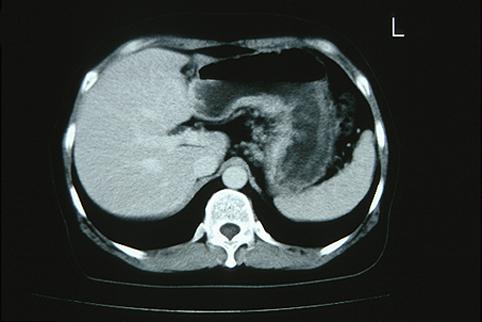

症例提示(所在地,施設名等): 福岡県・ 九州がんセンター

疾患(病理主体)の分類悪性上皮性腫瘍/腺癌

部位(臓器別)胃(部位)/体部

検査方法CT

腫瘍の肉眼分類3型(潰瘍浸潤型)/

病変の最大径(ミリ)40以上

腫瘍の深達度s(a)